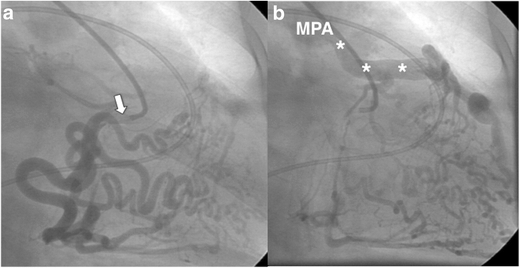

대동맥조영술: 확진

a. conventional RCA angiography 시행, 하부 collateral vessel이 발달

b. 수분 후 조영제가 LCA로 drain 되며 MPA 가 조영되는 소견